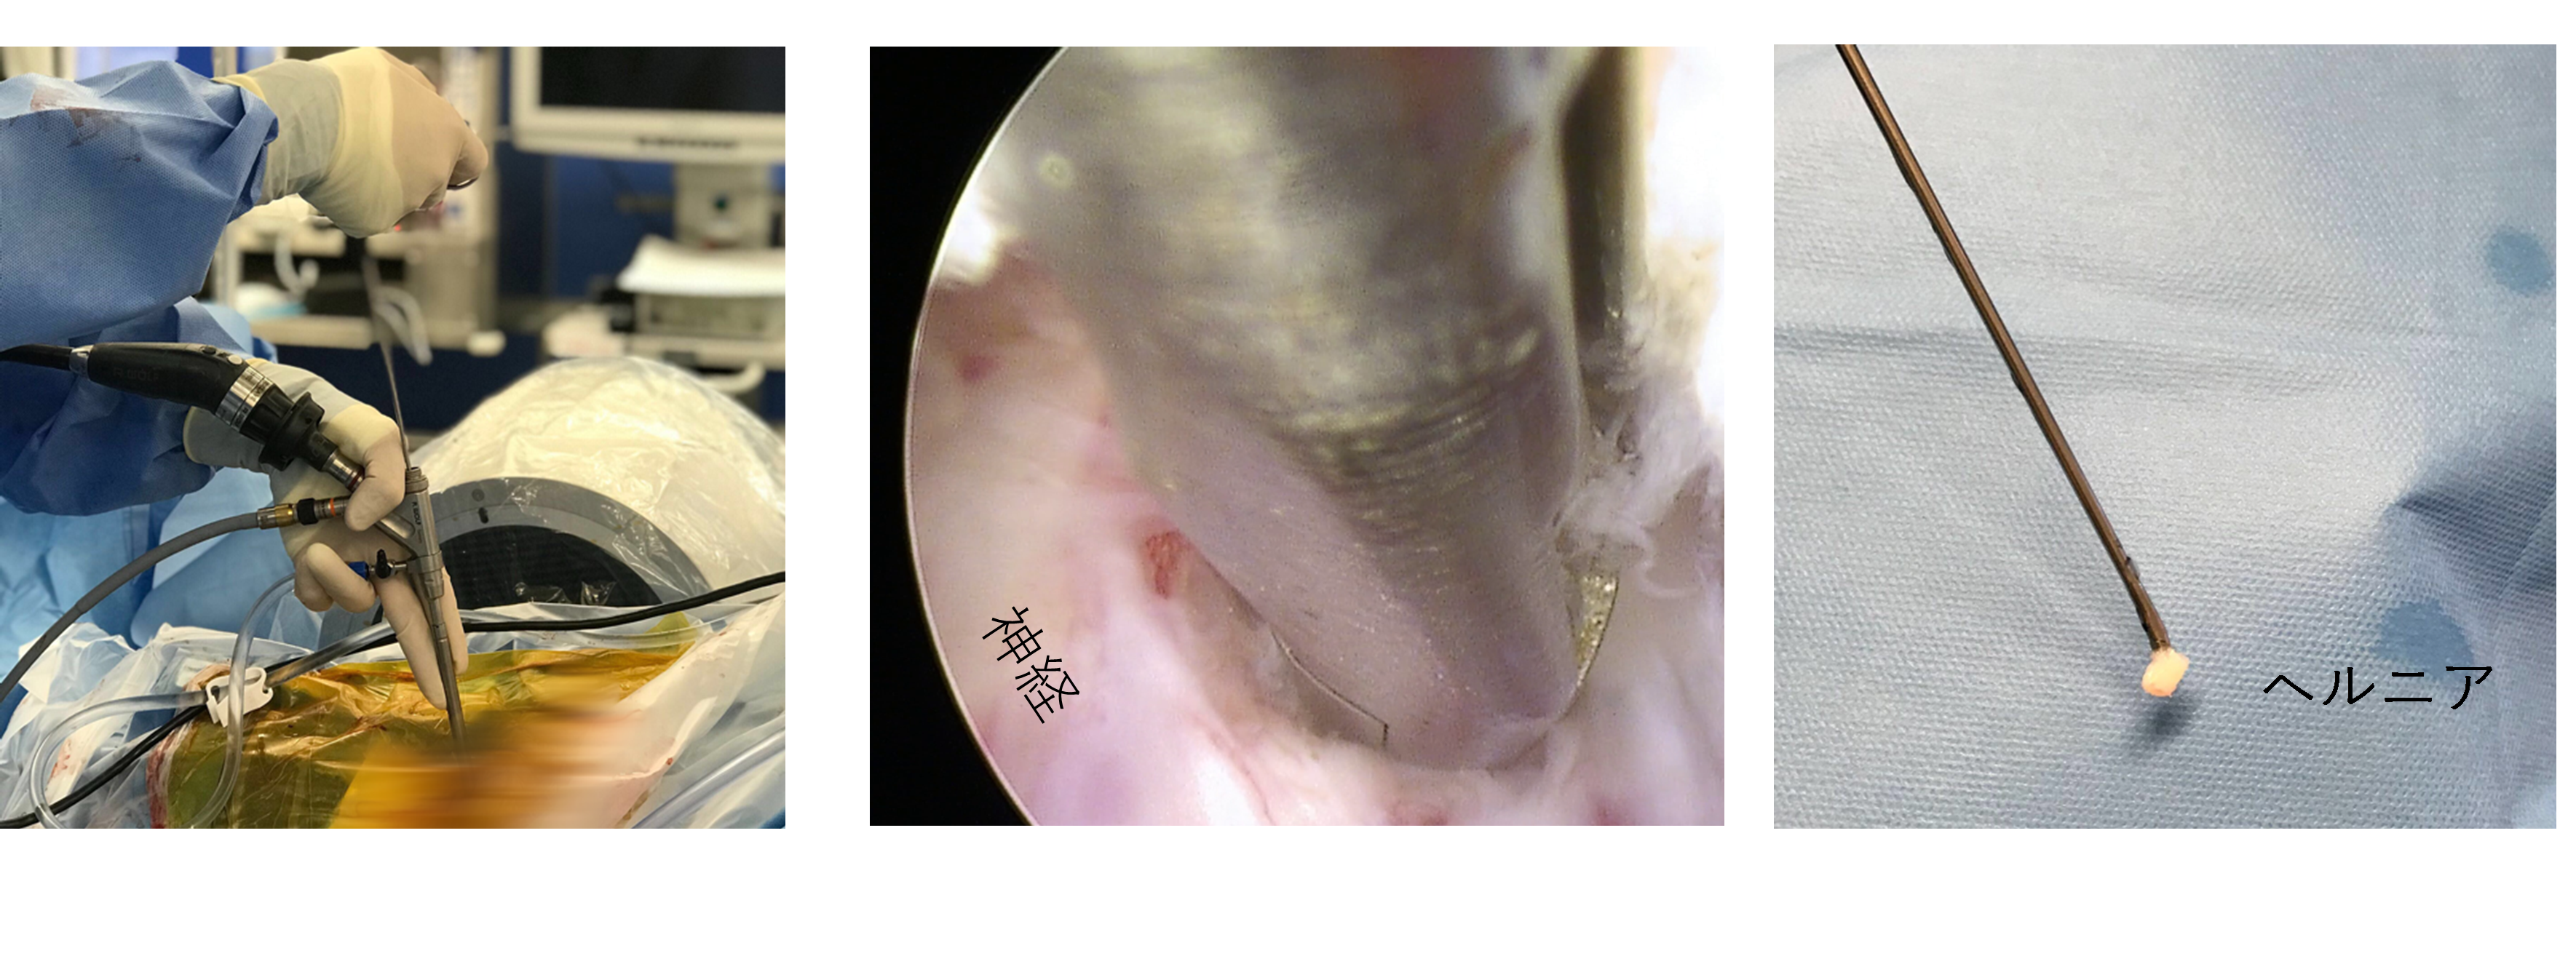

内視鏡下腰椎椎間板ヘルニア切除術 (Full-Endoscopic lumbar Discectomy:FED)

適応:腰椎椎間板ヘルニア

現在、本邦で行われている腰椎椎間板ヘルニアに対する最も低侵襲な術式です。当院では、多くのヘルニアをこちらの術式で治療することが可能です。直径8mmの内視鏡を背中から挿入して、モニターを見ながらヘルニアを切除します。そのため、傷口は1cm以下です。全身麻酔下に行いますが、術後3時間より歩行を開始し、多くの患者さんは2日後に退院可能となります。